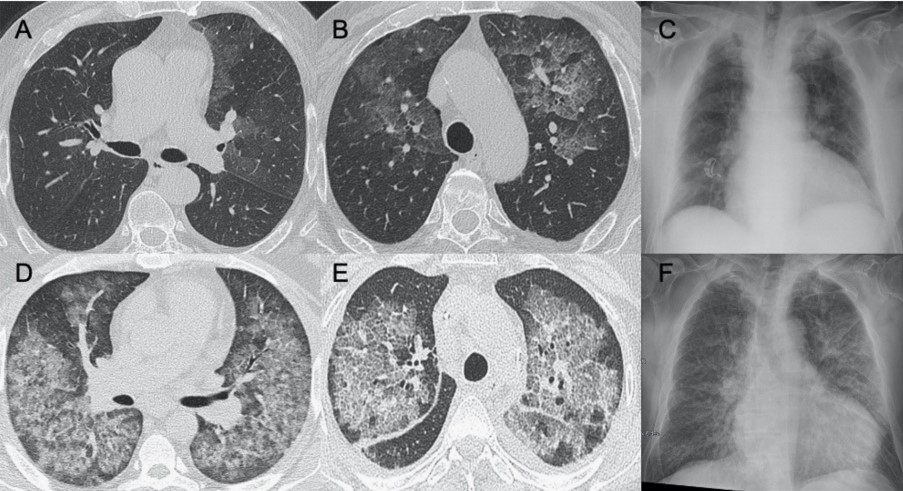

?甲型流感病毒

● CXR:雙側網狀結節狀影伴實變區,通常在下葉。

● CT:GGO多灶性實變和彌漫性區域,還可能觀察到淋巴結病變、空洞形成、胸腔積液。

圖3 圖(A-C)顯示了一例與COVID-19間質改變相似的甲型流感病例:GGO主要分布在胸膜下和雙側,呈小葉周圍性分布。圖(D)為同一患者的仰臥位胸片,可見彌漫性間質受累。

?HINI流感病毒

● CXR:單側/雙側GGO,伴或不伴實變區域,主要分布于支氣管血管周圍和胸膜下。

● CT:單側/雙側GGO,伴或不伴實變區域,主要分布于支氣管血管周圍和胸膜下。

圖4 圖(A-D)為一例H1N1相關肺炎并發急性呼吸窘迫綜合征(respiratory distress syndrome,ARDS)的影像,可見彌漫性和雙側GGO以及牽引性支氣管擴張。